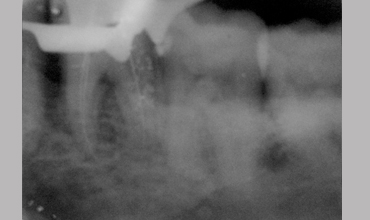

NON SURGICAL MANAGEMENT OF ENDODONTIC LESION AND SURGICAL MANAGEMENT OF PERIODONTIC LESION